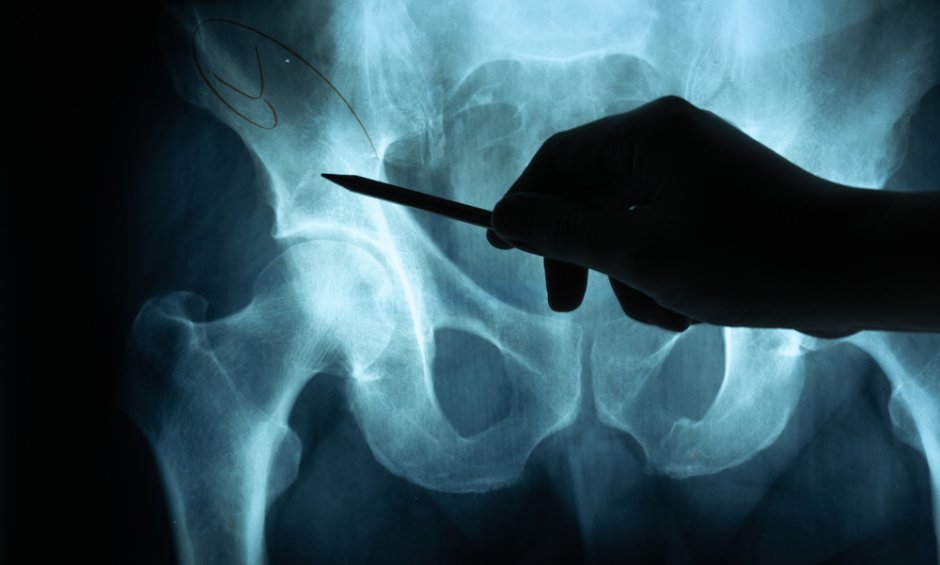

Η κύρια αιτία της οστεοαρθρίτιδας του ισχίου είναι η φθορά του αρθρικού χόνδρου. Γίνεται αντιληπτή ως πόνος, αρχικά μόνο όταν φορτίζεται η άρθρωση, αργότερα όλο και πιο συχνά και τελικά και σε κατάσταση ηρεμίας. Η αύξηση στην ένταση του πόνου είναι μια αργή διαδικασία, που διαρκεί χρόνια και μπορεί να οδηγήσει ακόμα και σε δυσκαμψία της άρθρωσης.

H αντικατάσταση του ισχίου (ολική αρθροπλαστική) φέρνει θεαματική ανακούφιση από τον πόνο και βελτίωση της λειτουργίας της άρθρωσης. Η ολική αρθροπλαστική ισχίου μετρά 70 χρόνια ιστορίας και αποτελεί μια συνηθισμένη και ασφαλή επέμβαση για τη θεραπεία της σοβαρής αρθροπάθειας, εξηγεί ο Βασίλης Βερναρδάκης, ορθοπεδικός χειρουργός, διευθυντής Γ΄ Ορθοπεδικής Κλινικής Ελάχιστης Επεμβατικότητας (MIS), Πιστοποιημένο Κέντρο Metropolitan General.

Ο χειρουργός μπορεί να έχει πρόσβαση στην άρθρωση του ισχίου από διαφορετικά μονοπάτια, ακολουθώντας μια «συμβατική» ή μια ελάχιστα επεμβατική χειρουργική προσπέλαση.

Η AMIS είναι Ελάχιστα Επεμβατική Χειρουργική Προσπέλαση του ισχίου και χαρακτηρίζεται από μειωμένη τομή του δέρματος και διατήρηση των μυών, των τενόντων, των αγγείων και των νεύρων. Αποτελεί ιδανική τεχνική ατραυματικής χειρουργικής, επιταχύνει την ανάρρωση και την αποκατάσταση και βελτιώνει την ποιότητα ζωής. Επίσης μειώνει τη συχνότητα των επιπλοκών.